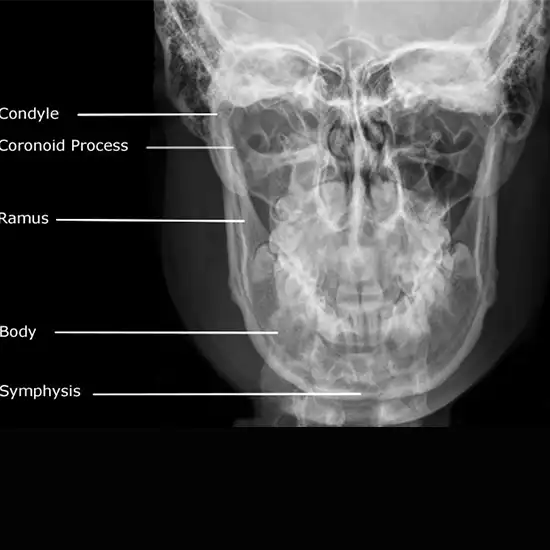

What is an X-ray Left Mandible AP & Lateral Test?

An X-ray of the mandible/Jaw (Left) (AP view) is typically obtained after a traumatic event to confirm a fracture or dislocation. If you've been in an accident and have these symptoms, see a doctor immediately.

• The primary purpose of this X-ray is to determine whether or not your mandible has been dislocated or fractured.

• To identify any probable jaw fractures or dislocations